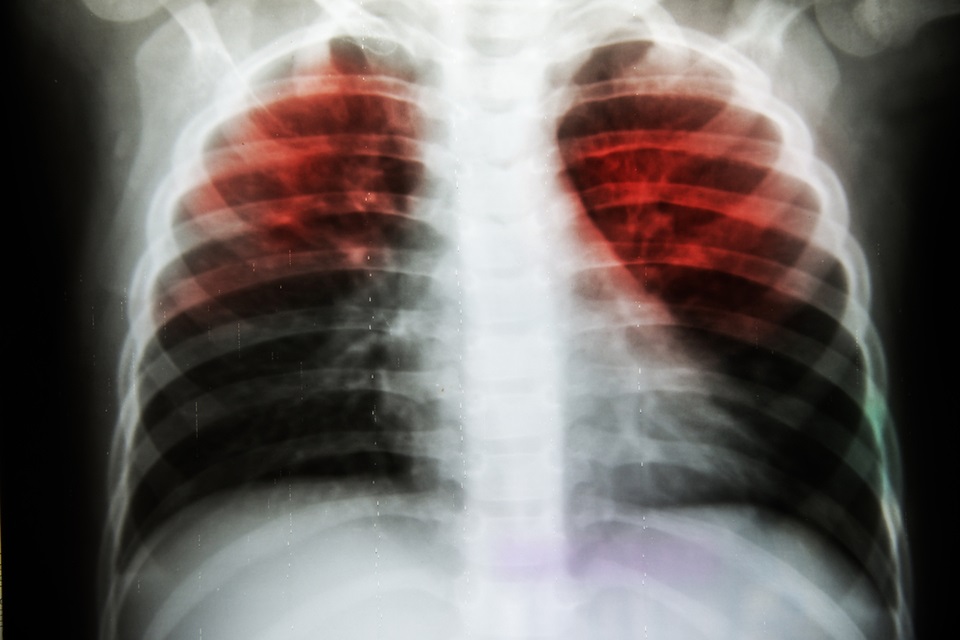

Researchers working to improve mental health of tuberculosis patients worldwide